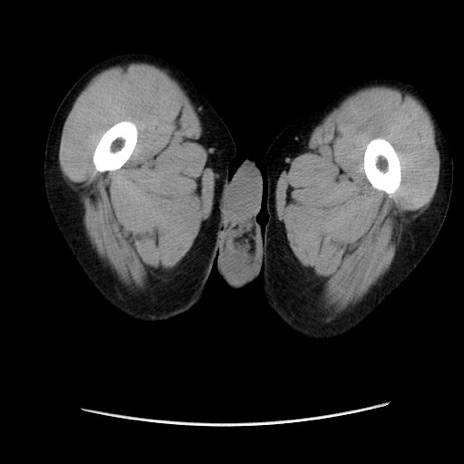

冠状断像